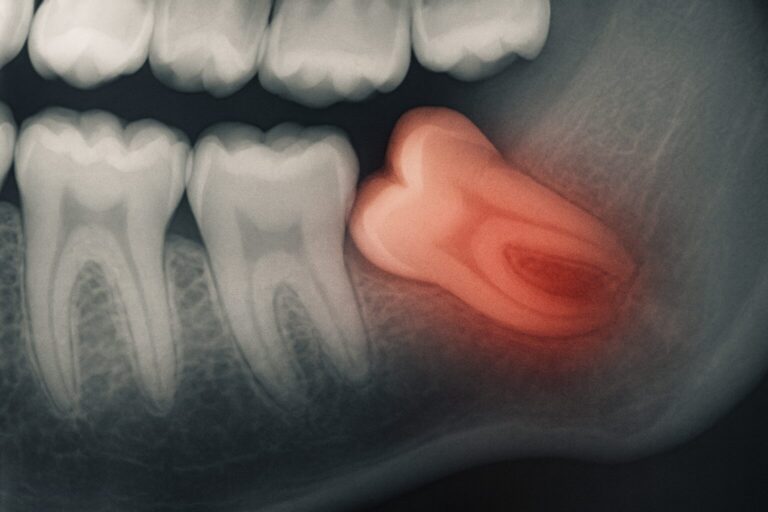

Chirurgiczne Usuwanie Ósemek Warszawa: Ekstrakcja Zęba Mądrości

W Dental-Cresco łączymy pasję i doświadczenie, aby zapewnić naszym pacjentom kompleksową opiekę stomatologiczną, w tym profesjonalne chirurgiczne usuwanie ósemek w Warszawie. Oferujemy komfortowe i bezpieczne zabiegi ekstrakcji zębów mądrości, przeprowadzane przez doświadczonych chirurgów stomatologicznych z wykorzystaniem nowoczesnych metod i znieczulenia dostosowanego do indywidualnych potrzeb każdego pacjenta. Wprowadzenie do tematu ósemek Co to jest ząb mądrości?…